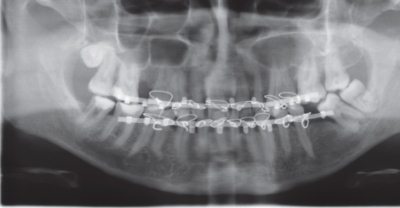

Проволочные шины изготавливали из алюминиевой проволоки индивидуально, припасовывая в полости рта, и фиксировали к каждому имеющемуся зубу бронзово-алюминиевой лигатурой. Ленточные шины изгибали по зубной дуге пациента и фиксировали к зубам бронзовоалюминиевой лигатурой. При смещении отломков накладывали межчелюстную резиновую тягу. После восстановления прикуса с помощью резиновых колец осуществляли межчелюстную фиксацию отломков в правильном положении (рис. 4).

Рис. 4. Ортопантомограмма. Больной Ф., 29 лет